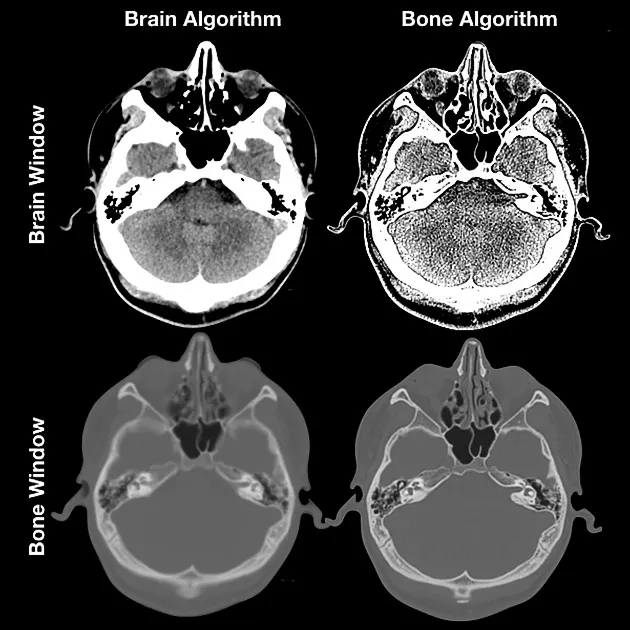

⭐ Windowing is key for interpretation. The vast range of Hounsfield Units is compressed into ~256 visible gray shades. The window width controls contrast, while the window level sets the central brightness point.

- **Window Width (WW):** The *range* of HU displayed. A narrow WW shows subtle tissue differences (e.g., grey vs. white matter).

- **Window Level (WL):** The *center* of the HU range. Set to the HU of the tissue of interest.

⭐ Stroke Window: For non-contrast head CT, a narrow window (WW 80, WL 40) is crucial to differentiate early ischemic changes from normal brain parenchyma.

⭐ Windowing is key. The same raw data is viewed with different brightness/contrast settings. A lung window (e.g., W:1500, L:-600) highlights parenchyma, while a mediastinal window (e.g., W:350, L:50) shows soft tissues.

- "Windowing" adjusts the greyscale to optimize viewing of specific structures like bone, lung, or soft tissue.